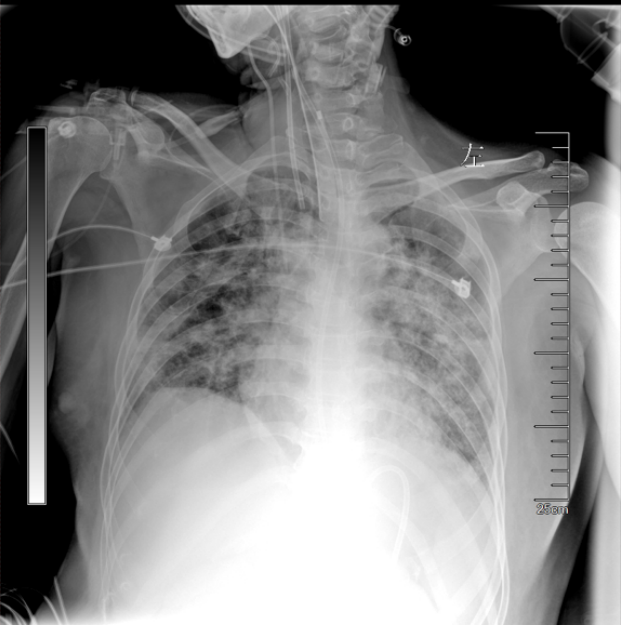

• 胸部X线片:双肺斑片样渗出,透亮度下降左肺较右肺偏重(图1)

图片

1  患者胸部X线片(2024-06-06)